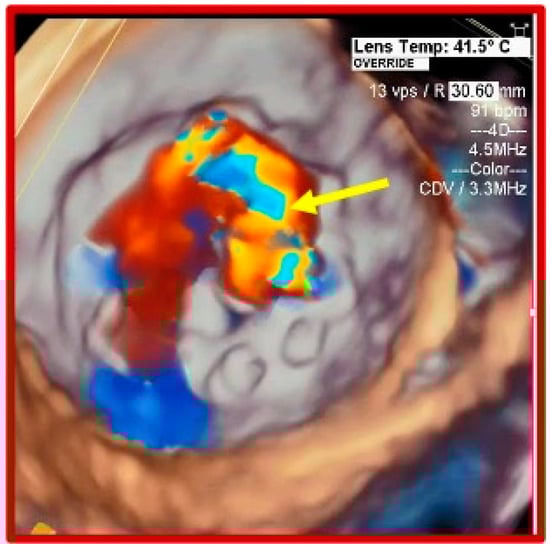

Early Basal Cuspal Tear of a Porcine Bioprosthetic Mitral Valve Causing Massive Mitral Regurgitation